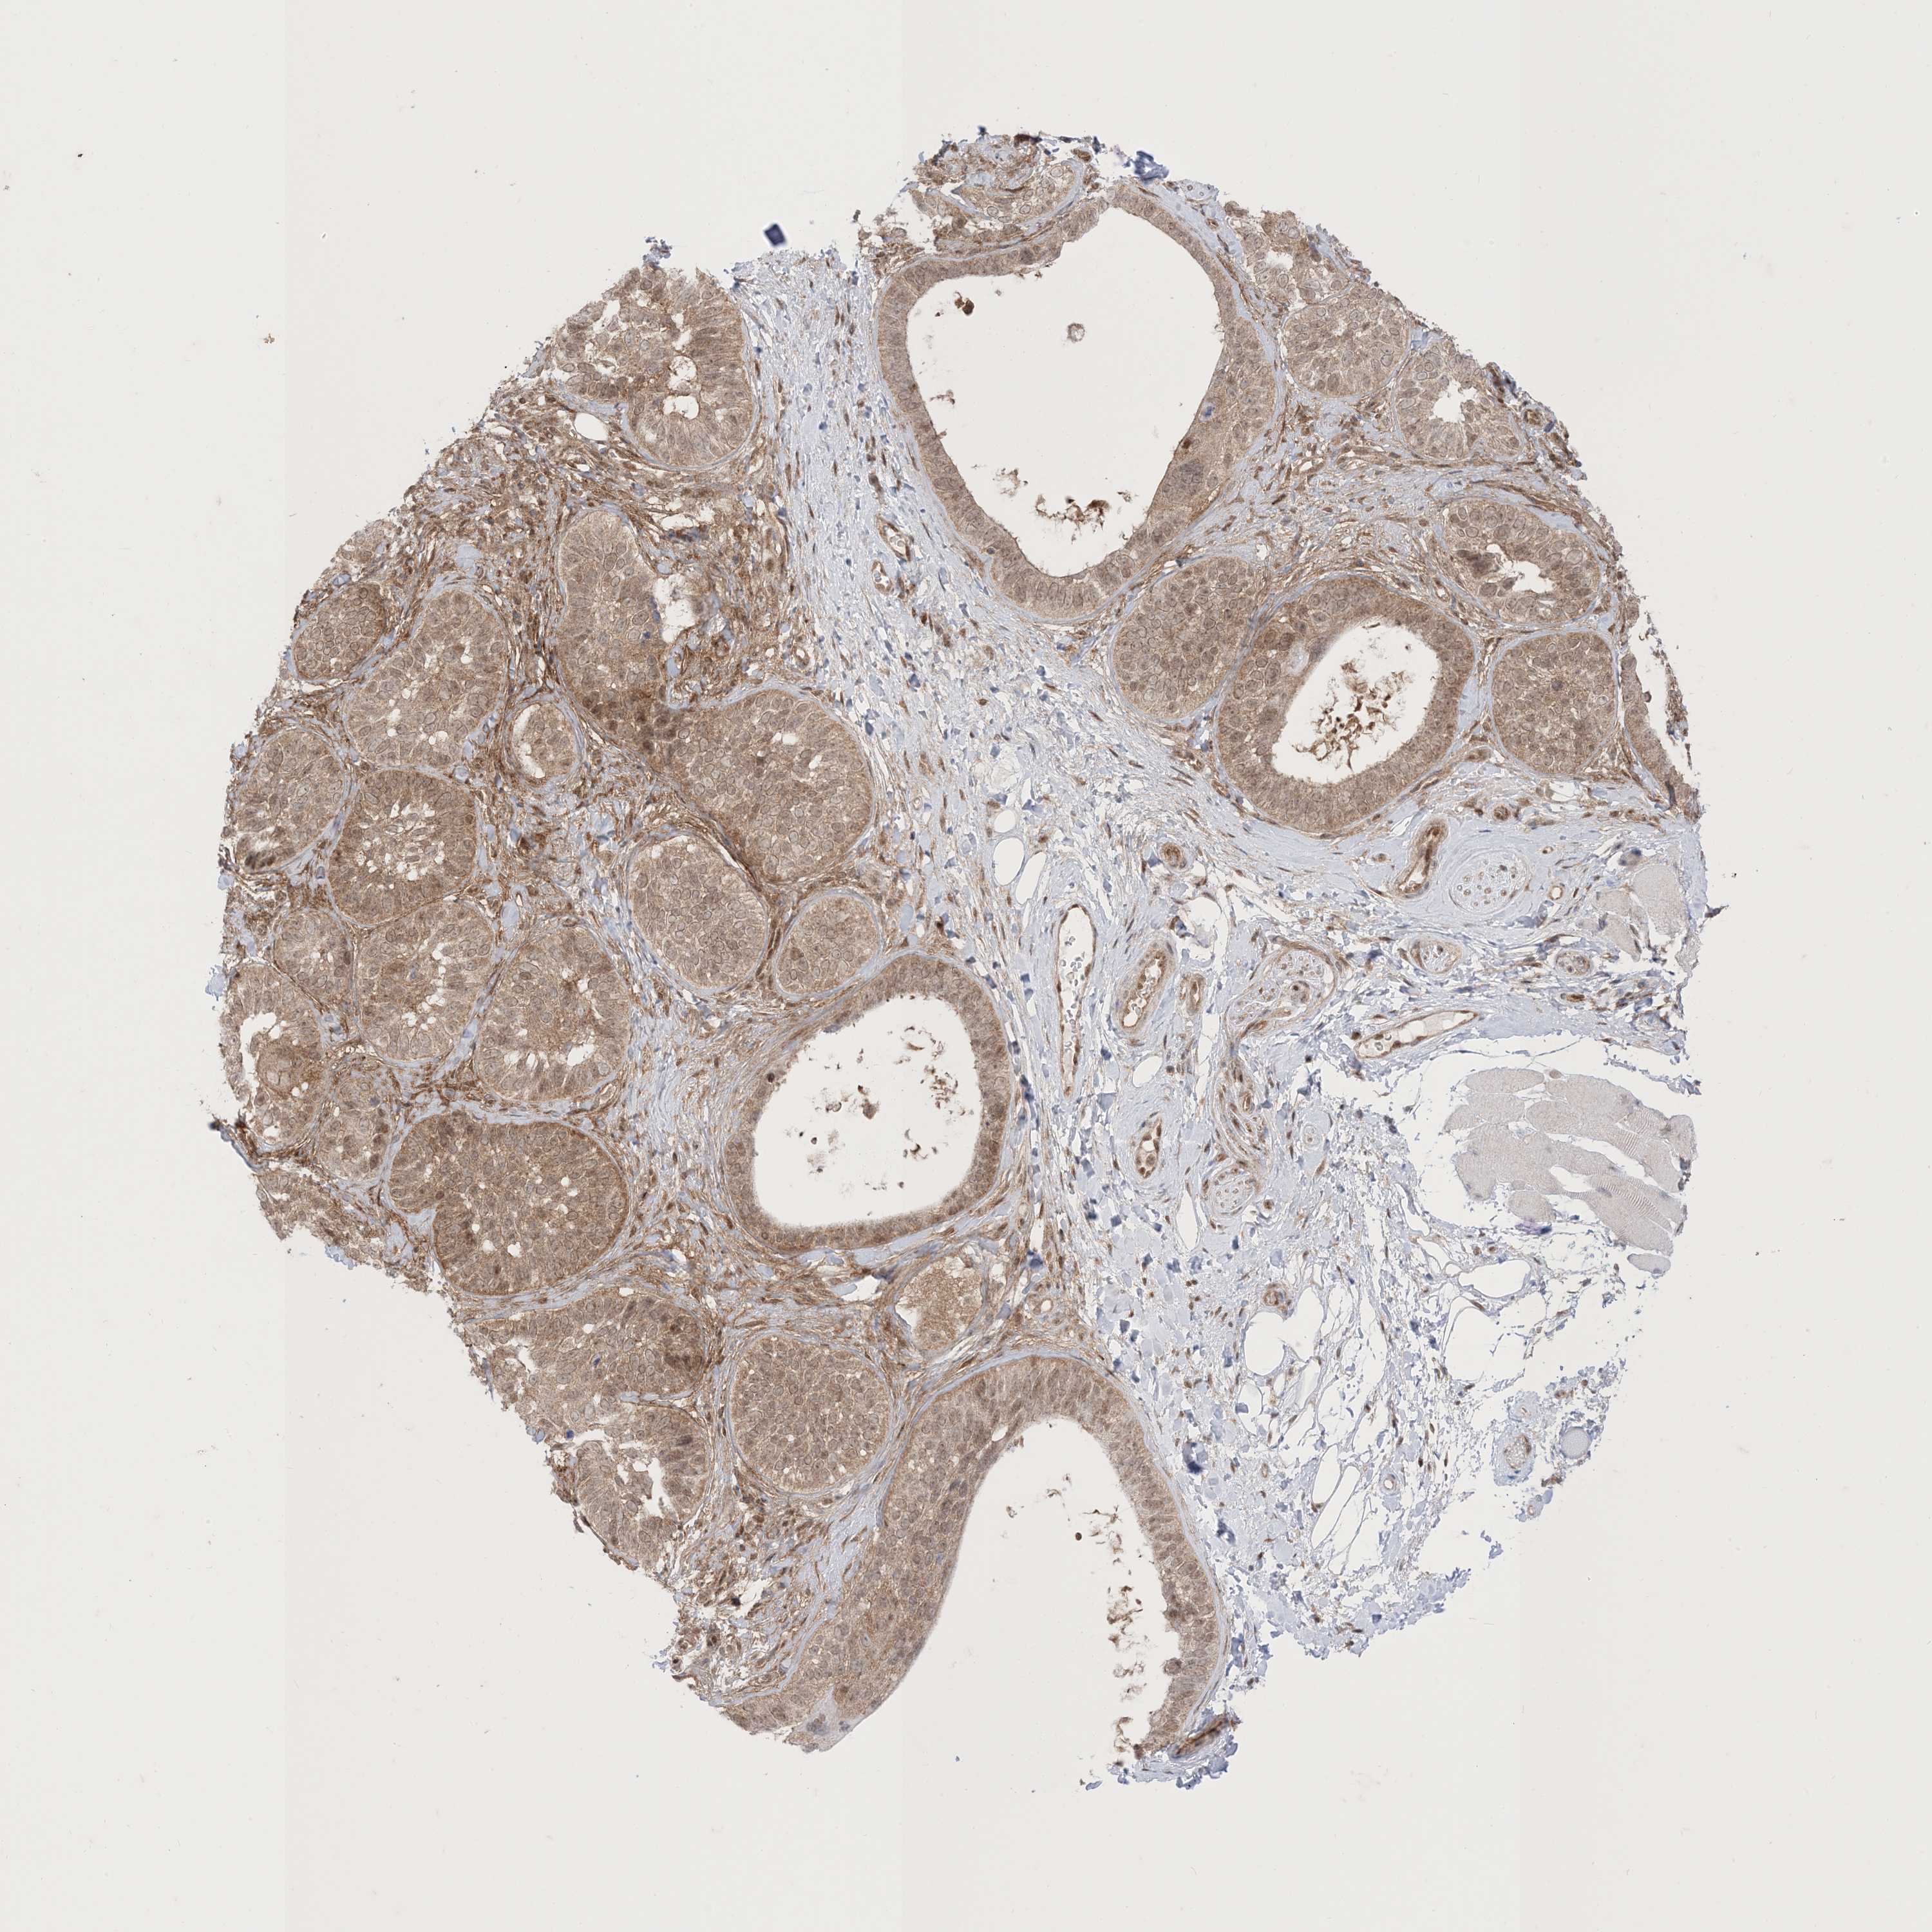

SKIN CANCER - Protein expressioni

A mouse-over function shows sample information and annotation data. Click on an image to view it in a full screen mode. Samples can be filtered based on level of antibody staining by selecting one or several of the following categories: high, medium, low and not detected. The assay and annotation is described here.

Each image is clickable and will lead to virtual microscopy that enables deeper exploration of all samples and also displays staining intensity scores, fraction scores and subcellular localization as well as patient and tissue information for each sample.

CAB022068

Papilloma, NOS